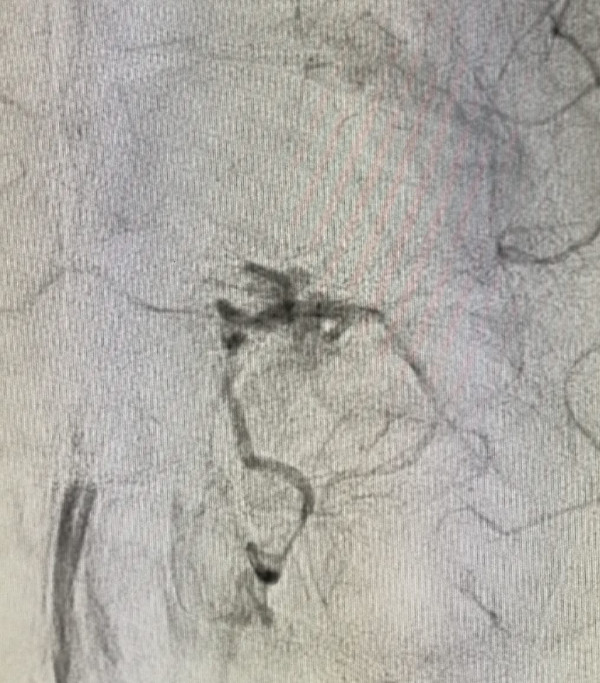

«Una MAV su questa arteria è rarissima e documentata da pochi casi in letteratura – spiega il prof. Concetto Cristaudo, direttore della Neuroradiologia dell’Azienda Cannizzaro e a capo dell’équipe che ha operato (nella foto) –. Il paziente era stato colpito da una emorragia nucleare antero basale e frontale posteriore sinistra, condizioni abbastanza gravi non tanto per la clinica silente quanto per la possibilità di un nuovo sanguinamento che avrebbe certamente portato alla morte. Di qui la difficoltà di riuscire a navigare strumentalmente questa arteria».

L’intervento, deciso dopo confronto con i neurochirurghi, è riuscito perfettamente. Grazie alla collaborazione del team di anestesisti, coordinato dalla dott.ssa Maria Concetta Monea, il bambino è stato sottoposto ad angiografia solo sedato con maschera laringea, e non intubato. Fondamentale anche la tempistica: i neuroradiologi interventisti, incrociati i dati con quelli della settimana precedente, hanno atteso il tempo minimo necessario che si detendesse l’emorragia e nello stesso tempo che si avesse certezza di intervenire sulla parte malata. «Si è trattato di un intervento ad elevatissimo rischio e complessità – aggiunge Cristaudo – con altissimo rischio di morte dovuto al materiale usato per il trattamento tramite catetere. Il bambino è stato embolizzato efficacemente, si è svegliato in giornata e il giorno successivo è stato ricoverato in Neurochirurgia». Ora gioca con i suoi videogiochi, mamma e papà accanto, e a breve potrà essere dimesso.